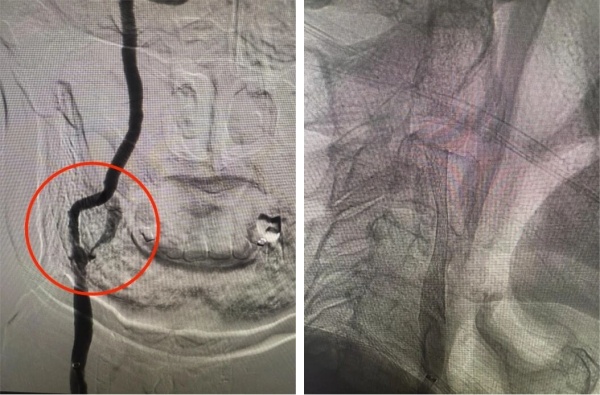

手术过程中,血管介入科团队以毫米级精度开展穿刺、置鞘、导引导管到位等步骤,精准地将微导丝穿过狭窄血管段,随后放置远端保护装置,如同为大脑血管筑牢“安全屏障”,有效预防术中斑块脱落引发栓塞。紧接着,选用合适规格的预扩张球囊对狭窄部位进行轻柔扩张,为支架植入开辟通路,随后将一枚自膨式支架精准送达狭窄段,缓慢释放并确认支架完全展开、贴壁良好。整个手术历时约60分钟,患者术后造影显示,患者颈内动脉狭窄部位血流完全恢复通畅,无残余狭窄,手术达到了团队预期的效果。

上图为手术过后血管狭窄明显改善,症状改善

手术过后,我院护理团队接过接力棒,运用中医疗法为患者提供护理服务。患者术后24小时即可自行床上活动,头晕、肢体乏力症状明显缓解,未出现任何手术并发症。术后2天,患者各项生命体征平稳,能够自主下床活动,饮食、睡眠恢复正常,顺利康复出院。出院时,患者及家属紧紧握住医护人员的手,对我院医护团队表达了发自内心的感谢。